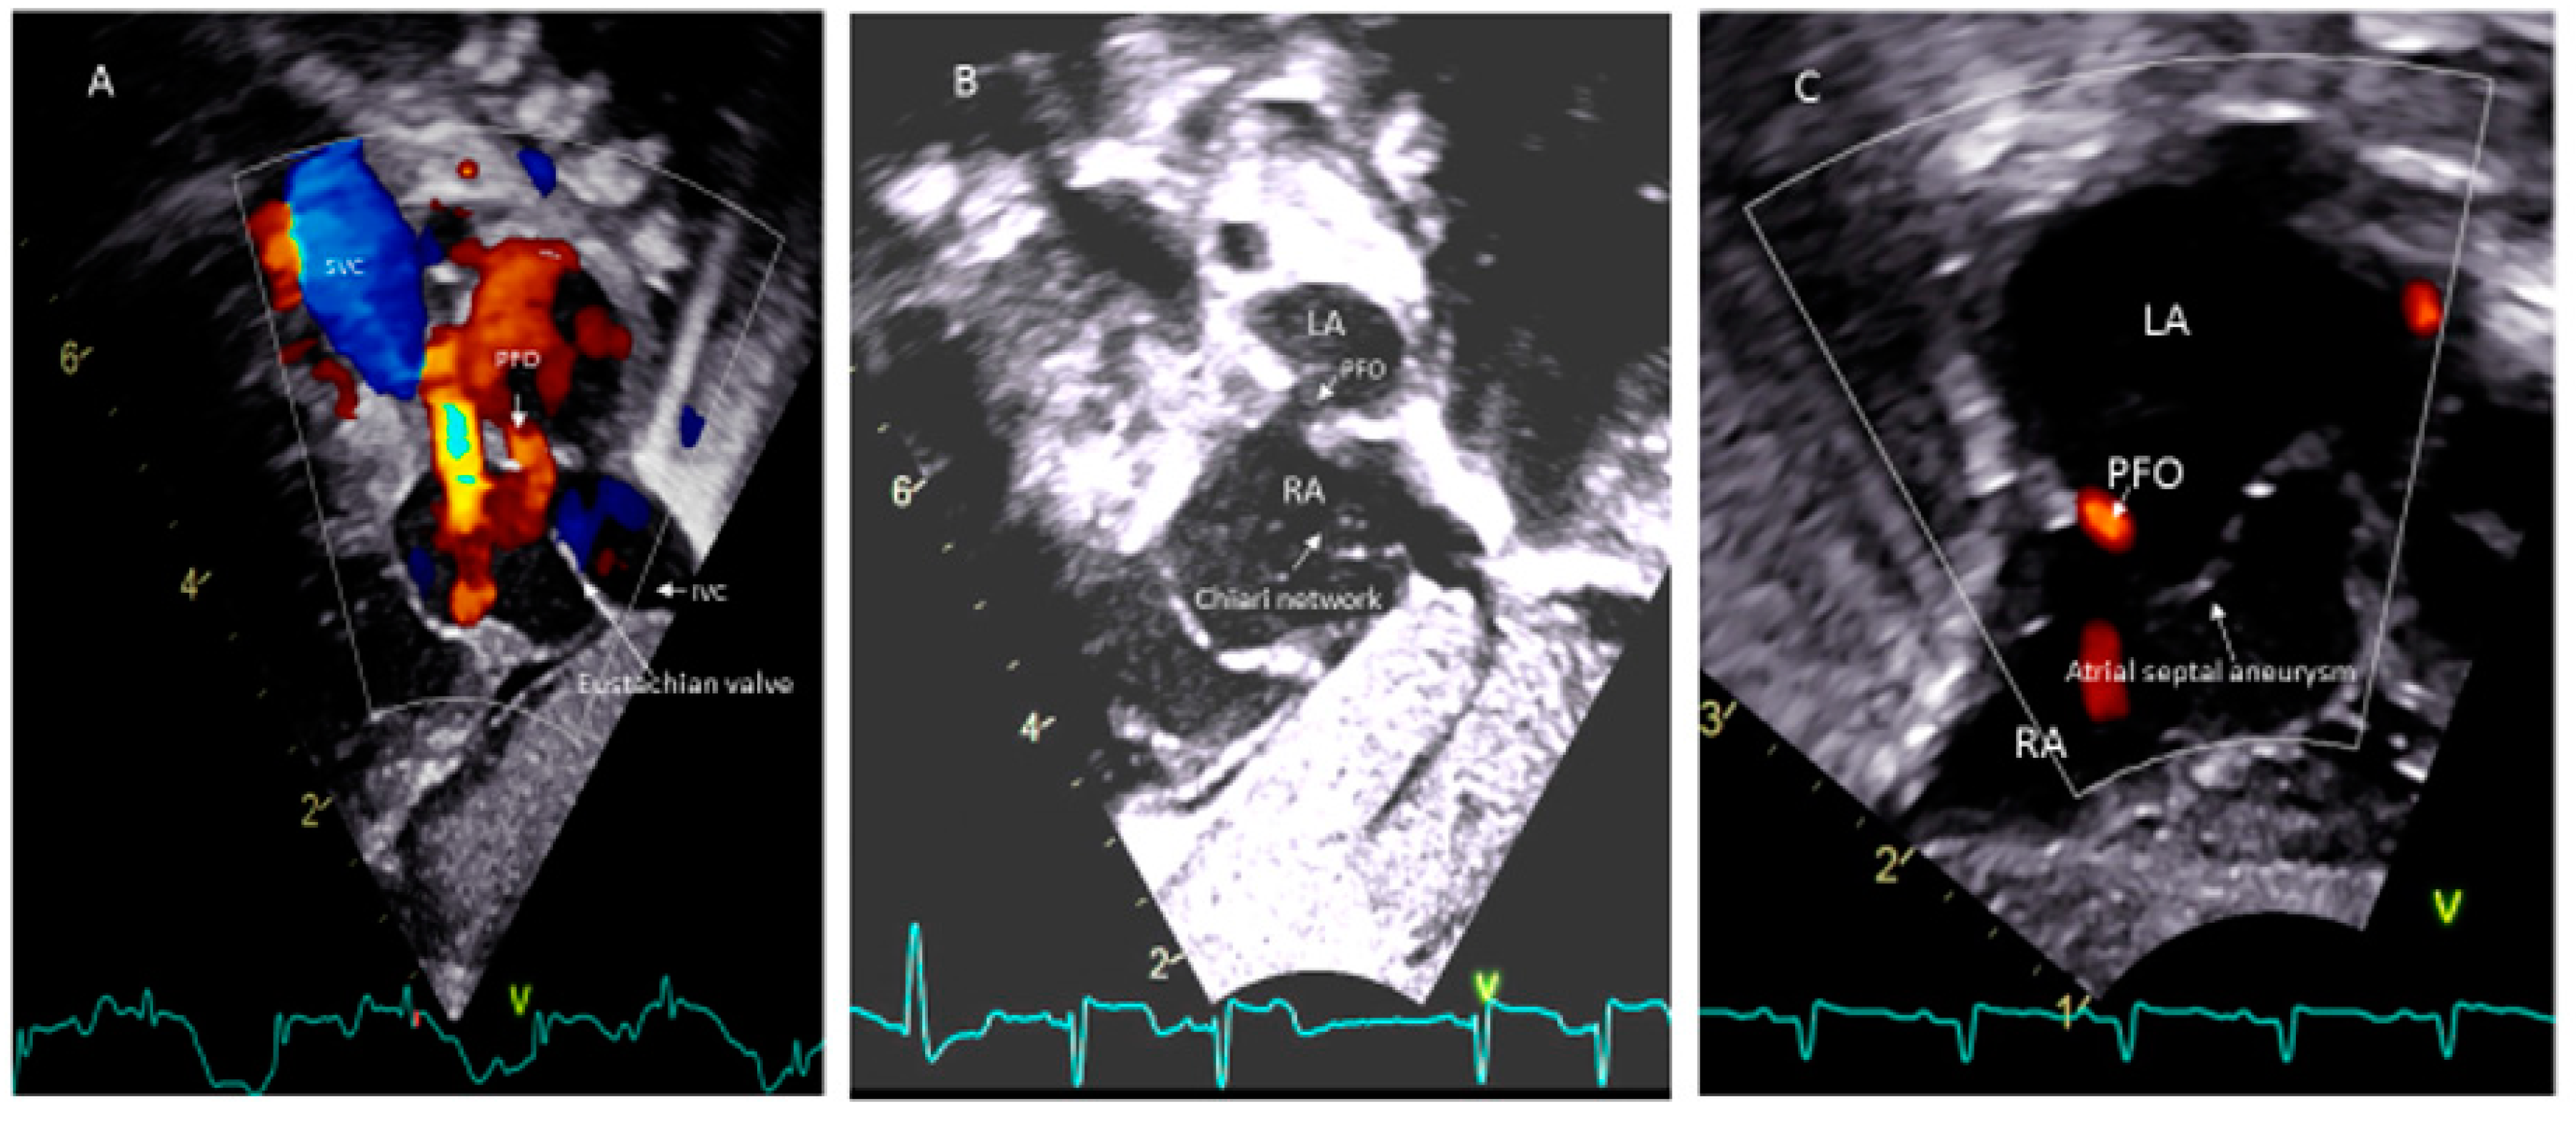

- Silvestry, F.E. Guidelines for the echocardiographic assessment of atrial septal defect and patent foramen ovale from the American Society of Echocardiography for cardiac angiography and interventions. J. Am. Soc. Echocardiogr. 2015, 28, 910–985. [Google Scholar] [CrossRef]

- Rana, B.S.; Shapiro, L.M.; McCarthy, K.P.; Ho, S.Y. Three-dimensional imaging of the atrial septum and patent foramen ovale anatomy: Defining the morphological phenotypes of patent foramen ovale. Eur. J. Echocardiogr. 2010, 11, 119–125. [Google Scholar] [CrossRef]

- Schneider, B.; Hofmann, T.; Justen MHMeinertz, T. Chiari’s network: Normal anatomic variant or risk factor for arterial embolic events. J. Am. Coll. Cardiol. 1995, 26, 203. [Google Scholar] [CrossRef]

- Rigtelli, G.; Dell’avvocata, F.; Braggion, G.; Giordan, M.; Chinaglia, M.; Cardaioli, P. Persistent venous valves correlate with increased shunt and multiple preceding cryptogenic embolic events in patients with patent foramen ovale: An intracardiac echocardiographic study. Catheter. Cardiovasc. Interv. 2008, 72, 97. [Google Scholar] [CrossRef]